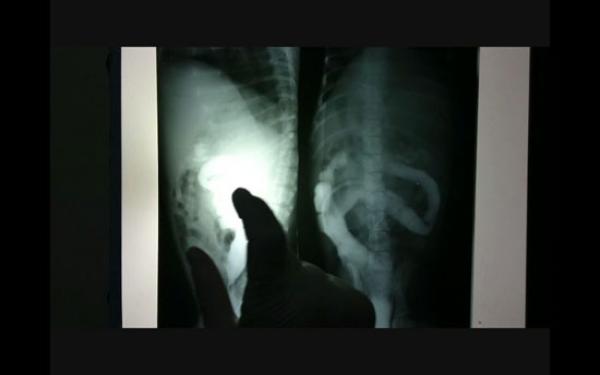

و وفق يومية الأخبار، فقد تقدمت الضحية نادية، التي عاشت بأدوات طبية داخل رحمها لخمس عشرة سنة، بسبب خطأ طبي إثر عملية جراحية بقسم التوليد بمستشفى الحسن الثاني بأكادير، إلى المحكمة الإدارية بالمدينة بطلب خبرة مضادة خارج أكادير، بعدما رفعت دعوى قضائية ضد الطبيب الذي أشرف على توليدها، حفاظا على موضوعية الخبرة.

و تابعت نفس اليومية أن الخبرة الأولى التي تم إجراؤها اعتبرتها الضحية منحازة للطبيب المولد، على اعتبار أن الخبرة الأولى المنجزة تقول إن رحم المشتكية يعاني من اختلالات في التوازن الهرموني، وليس بسبب الأدوات الطبية الموجودة في بطنها، لتطالب نادية بخبرة مضادة.